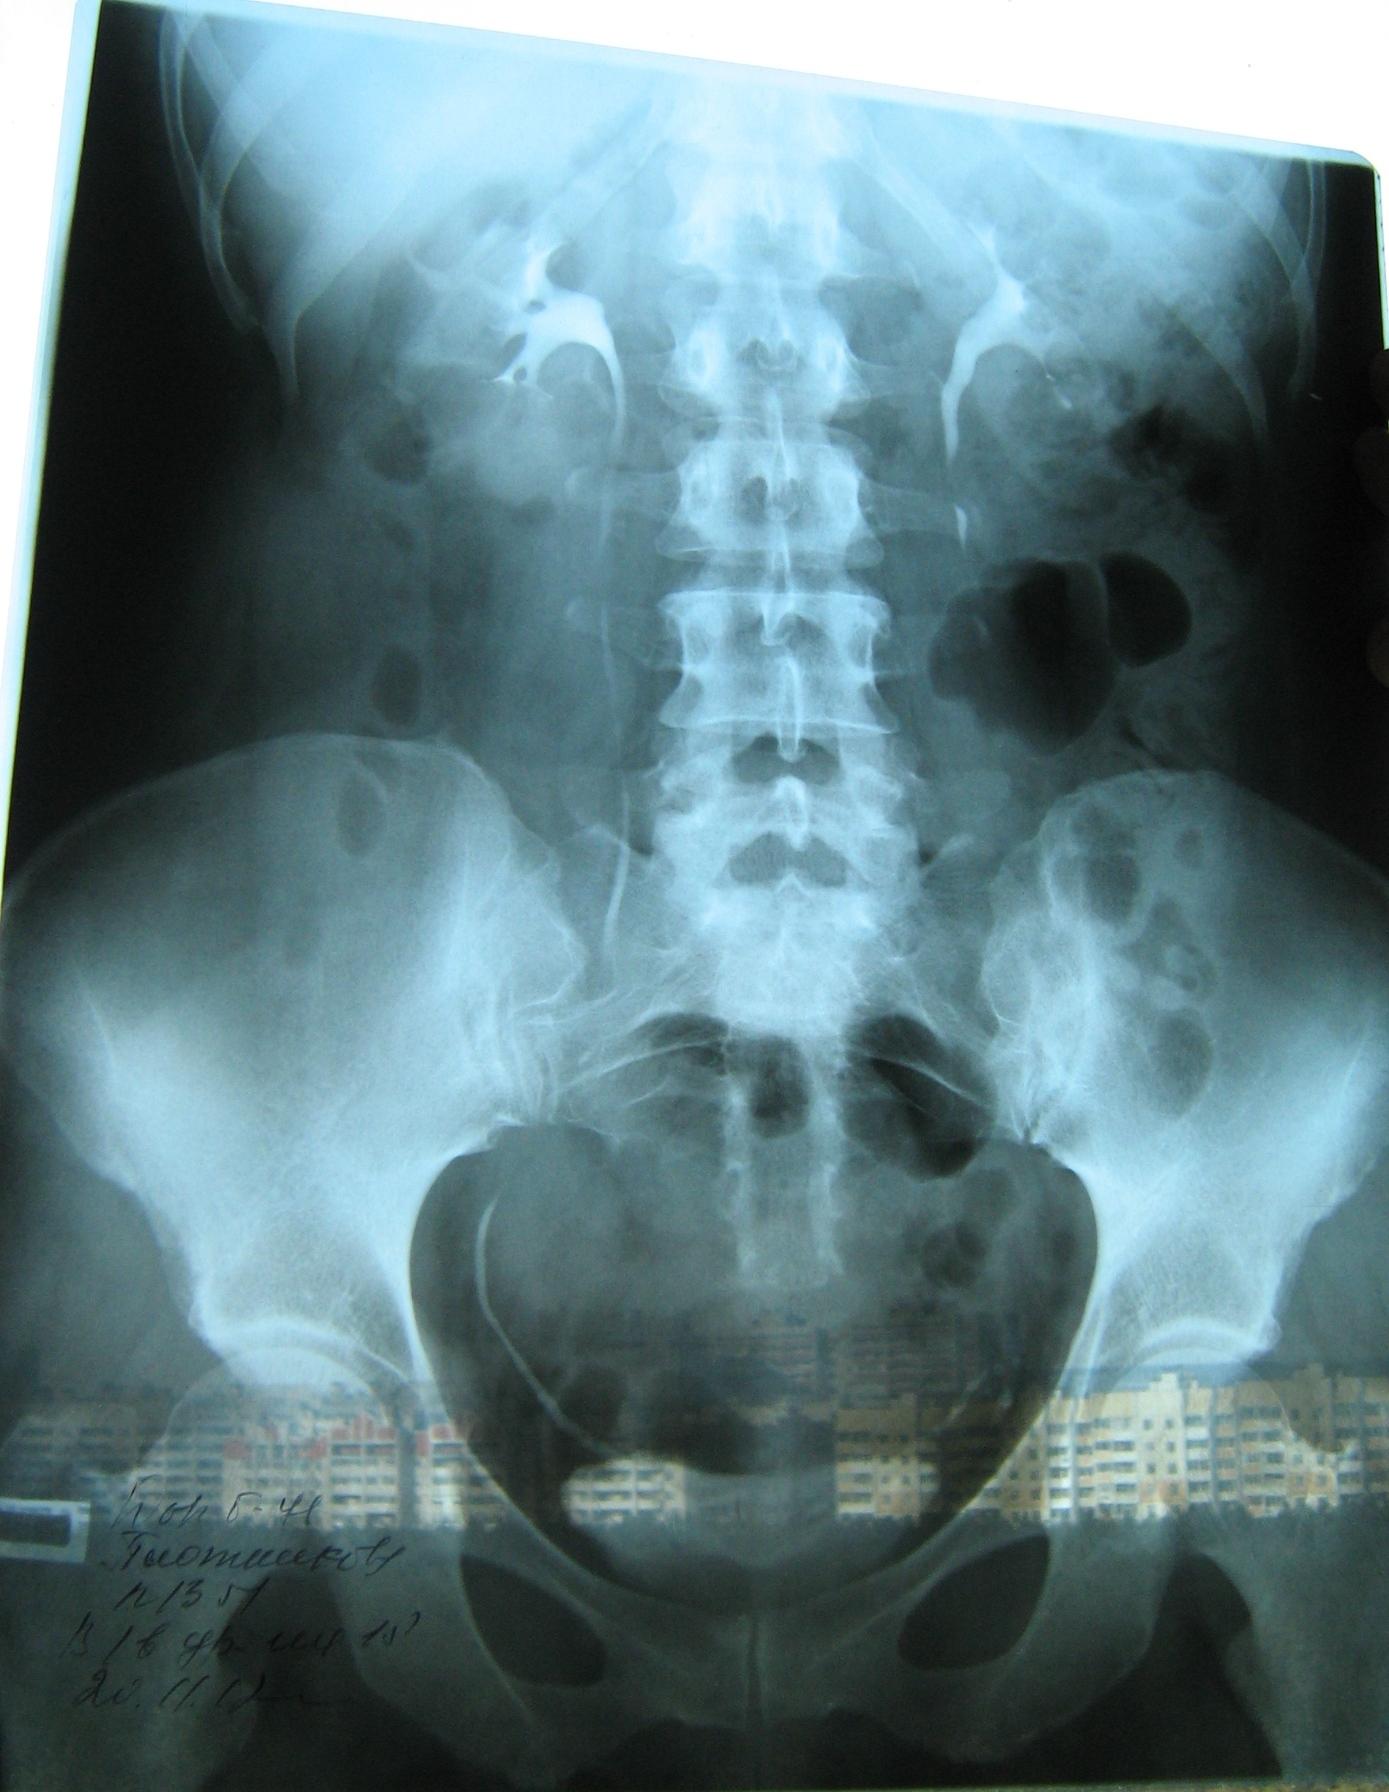

Была сделана операция 04.07.2012г по поводу нефропексии правой почки поясничной мышцей с помощью разреза. После операции болит правая сторона живота и в спине и в пояснице был затронут нерв, и до сих пор правая нога до колен не отходит спереди и сбоку. Через полтора месяца после операции образовался отек, пошло воспаление сзади на спине, потому что был затронут нерв. Сделала урографию через 4 месяца после операции. Если вас не затруднит, посмотрите пожалуйста снимки, правильно ли располагается мочеточник правый после операции. Скажите пожалуйста, посмотрев мои снимки, правильное ли расположение мочеточника и почему болит правая сторона живота все это время, и каким исследованием теперь после операции проверить что там творится в животе, что там затронуто? Все указывает на то что был затронут нерв, оперирующий врач говорит что не может быть такого, а я уже почти всю ногу правую не чувствую

Снимки прикрепляю

Абсолютно нормальное расположение почки и мочеточника . Но ведь и онемение нижней конечности с положением почки не связано. Есть такое понятие "футлярный синдром"- после вынужденного положения конечности. Проконсультируйтесь с неврологом.